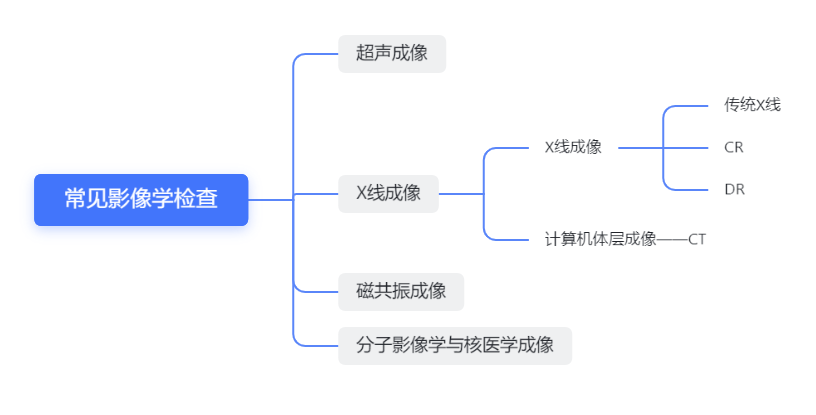

X射线是一种特殊的放射性光,具有透视图,可吸收性等。使用X射线成像的技术称为X射线成像技术,主要包括X射线成像和X射线计算机层析成像(CT)。在生活中,通常使用“ X射线”来指代“ X射线成像”,而CT则用于指代“ X射线计算机 - 倾斜成像”。当然,在谈论本段之后,您应该对我感到困惑。没关系。首先将关系图放在此处,然后我将以最粗糙,最简单的方式解释它。

X射线成像 - 传统X射线,CR和DR

让我们首先了解X射线成像的原理。 X射线是具有极短波长的电磁波,具有穿透性,可吸收性,荧光和光敏作用。 X射线成像的基本原理(常见版本)是开元ky888棋牌官方版,当X射线照射人体时,由于人体不同组织的密度和厚度不同,X射线的吸收程度也不同,因此它们最终显示出不同的黑白(通常称为不同的密度)图像。 X射线成像主要包括传统的X射线,计算机X射线成像(CR)和数字X射线成像(DR)。这三个之间的主要区别在于成像技术的差异。传统的X射线是在胶卷上成像的,而CR和DR是像素化的图像和数字化图像。其中,DR成像时间很短,它可以执行荧光镜检查和随后的图像技术处理以及其他高级功能,这些功能广泛用于临床应用中。上述技术的选择和应用会受到主题状况,医院和医疗保险的实际状况的影响。所有X射线检查。

在生活中,读者对X射线有一定的了解。他们可能知道白色是骨头,而灰黑则是其他。

不同的组织和部分呈现不同的颜色,实际上与组织密度直接相关。组织密度越高,吸收X射线的越多,并且最终图像颜色越亮。因此,在X射线成像中,白色部分称为高密度,灰黑称为低密度。如果人体会导致损伤变化组织密度,则在达到一定水平后成像时将以黑色,白色和灰度变化。

X射线成像是一个覆盖图像,即从X射线照射部分的前后到后面的所有图像的叠加,就像“感应眼”的角度。因此,X射线成像也称为荧光镜检查。例如,用于学校体格检查的“胸部荧光镜”项目,公务员和公共机构的参加体格检查是指胸部来回的X射线成像,但它不显示电影中的图像,成像板和平板电脑。在检测器中,它直接在荧光屏幕上显示以实时观察。下图是胸部来回的X射线图像,这表明胸部的所有组织结构都叠加在图像中。

图片来自第九版的Renwei医学成像